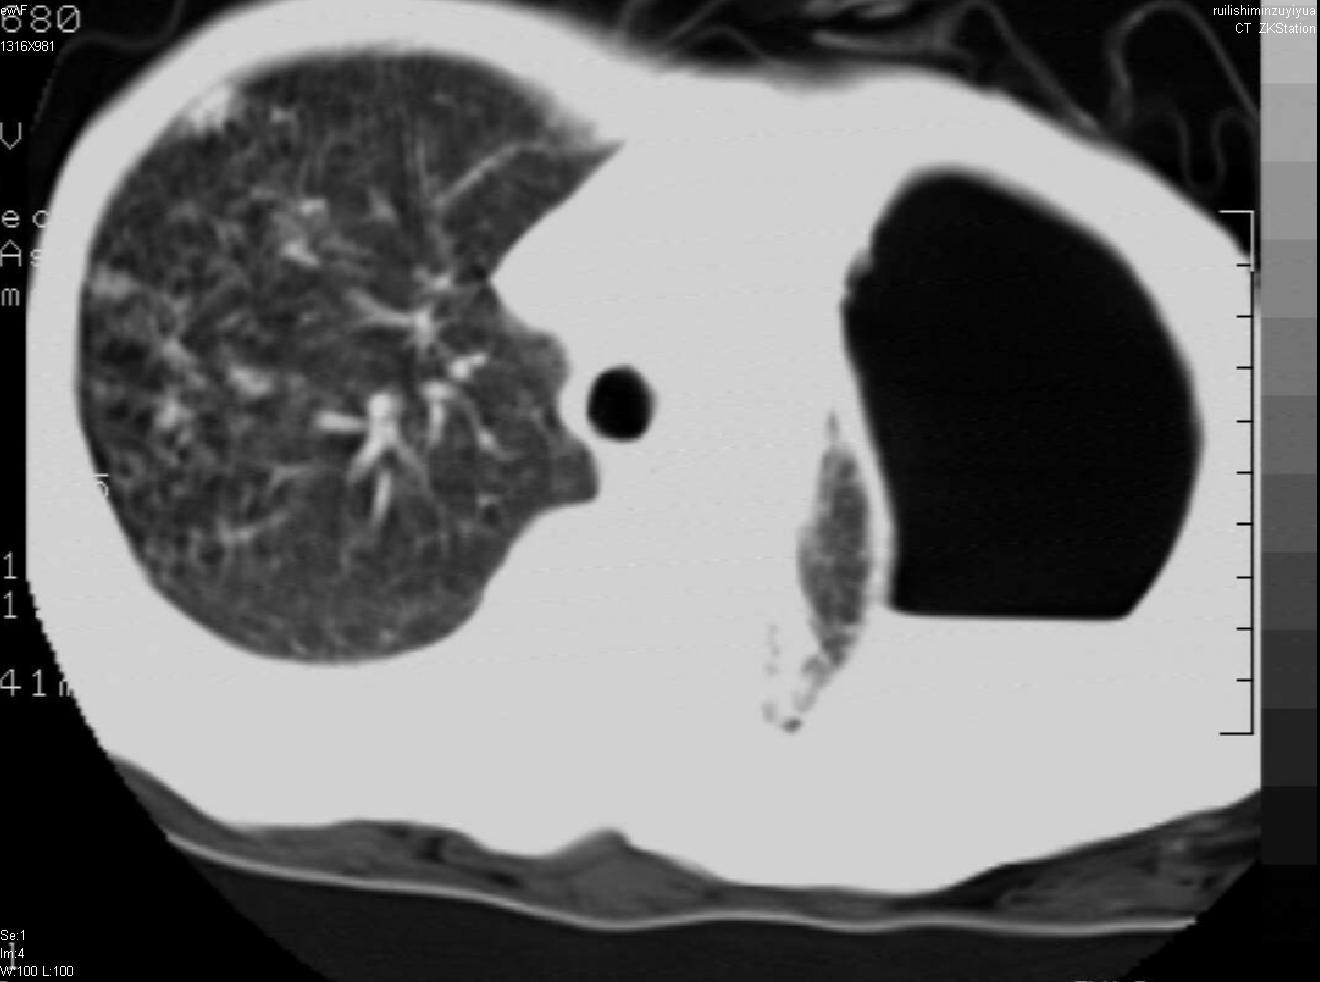

以下是引用天南地北在2007-6-11 23:32:00的发言:[br]1:左侧肺毁损(结核性)伴感染(多发空洞伴液平面)。[br]2:右肺继发型肺结核。

以下是引用avril在2007-6-12 1:17:00的发言:[br]1、左肺毁损。[br]2、左肺多发肺大泡伴自发性气液胸形成。[br]3、右肺继发型结核。

以下是引用尚峰在2007-6-11 22:44:00的发言:[br]慢阻肺、肺纤维化、肺大泡、气胸形成,此患者有没有急性病史?